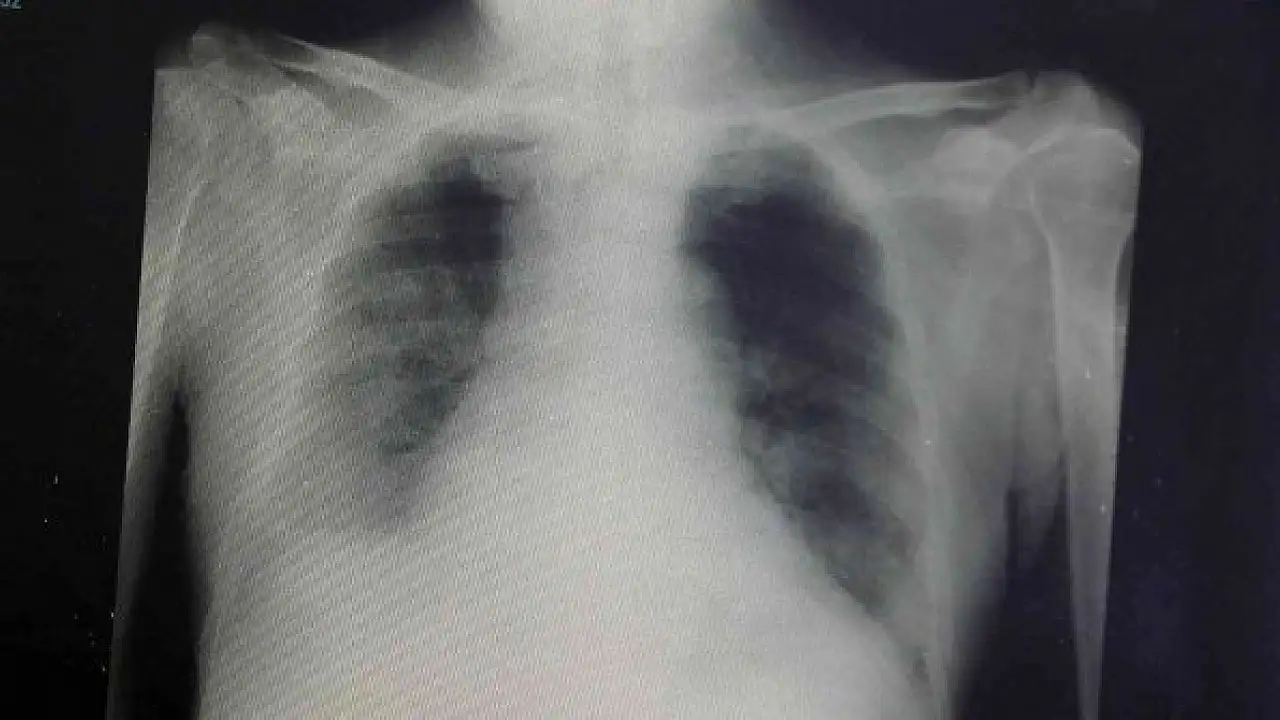

Son olarak varyantların akciğer tutulumları hakkında da bilgiler veren Dikmen, şunları söyledi:

"Delta varyantına yakalanan hastalarda akciğer tutulumunun daha fazla olduğunu görüyoruz. Omicron varyantına yakalanmış bir hastanın akciğer filmine baktığımızda ise deltaya göre çok az kaldığını görebiliyoruz. Bu da omicron geçiren bir hastanın, delta varyantına yakalanan bir hastaya göre daha rahat nefes aldığını gösteren bir durumdur."